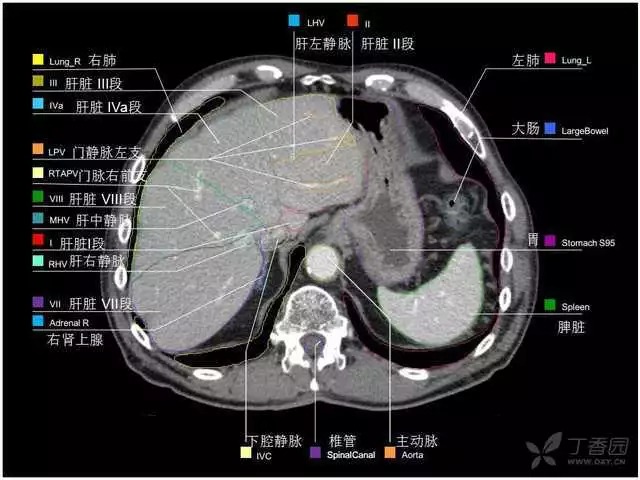

腹部肝脏高清CT断层的图谱

全腹部高清CT图谱,淋巴结彩色图谱,血管解剖图谱大汇总!

超声肝脏分叶及分段

肝脏分段和基本解剖学标志